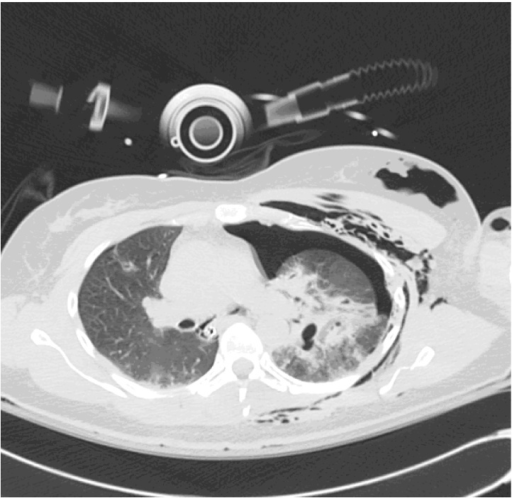

Traumatic bronchial injury International Journal of Surgery Case Reports